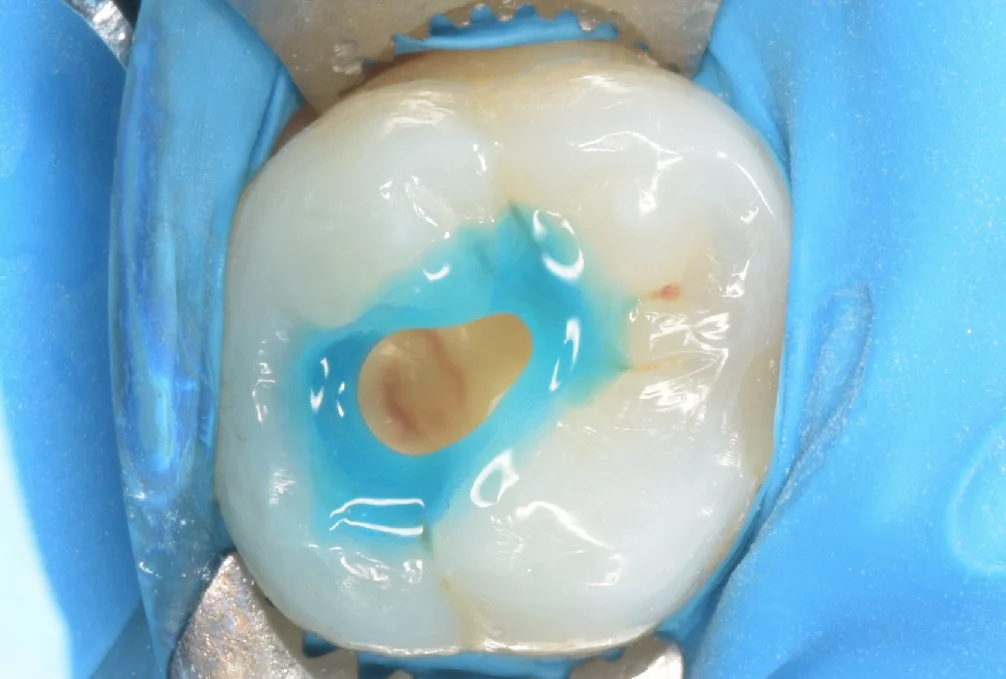

古い詰め物だけ除去して虫歯が見えやすい状態にしたのがこちらになります。

真ん中あたりの古い詰め物の下は普通に虫歯になっている状態でした。

今回最も問題としては大きかったのが、後ろ側の比較的真新しい詰め物の方で、虫歯の除去は問題なく行えているように見えますが・・・

詰め物を外していく際に少し削ったら残りの部分が飛んでいきました。

毎回セミナーでもお伝えしているのですが、深部がしっかりと歯と接着されていないと違和感が生じます。

様々な問題で歯と詰め物との間が接着不良になることはありますので、色々と気をつけながら治療を行う必要がありますね。

ここら辺がレジン修復がテクニカルセンシティビティ・・・即ち術者によって大きく予後が変わると言われている部分ですね。

虫歯を取り切りました。

しっかりと歯の本来の色になりました。

左側の元々大きな詰め物が入っていた方は別に虫歯というわけではなかったのですが、漏洩により感染していた可能性が高かったですので、一層削っています。

ゴムのマスクをつけて再表層の処理をしているのがこちらです。

歯の再表層のみを酸性の薬液で処理することで強い接着を得られるようにするという、セレクティブエナメルエッチングという手法があるのですが、これを行うと行わないで、後々辺縁の着色が生じづらいと言われています。

ただ注意すべきは過剰にやりすぎると良くないのと、内部の象牙質という層についてしまうと接着力が大きく落ちてしまうため、非常に繊細な動作が必要になります。

私は象牙質についても接着力の低下があまり生じない薬剤を使用しているので、割と大雑把に表面処理を行なっています。